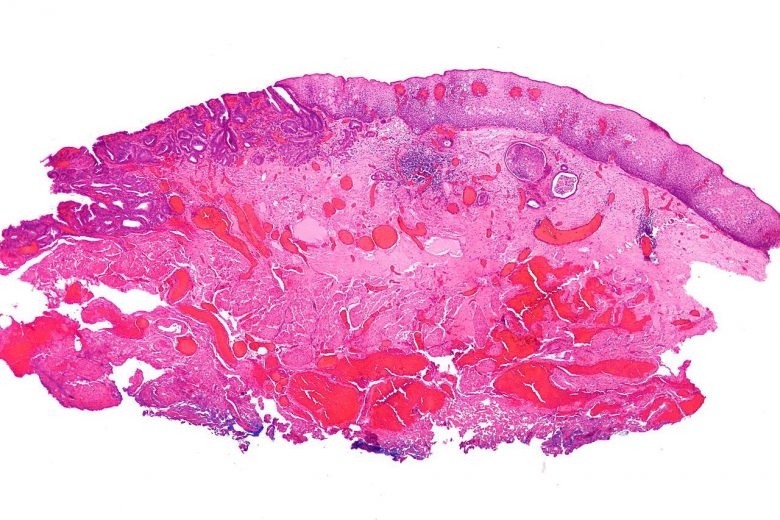

Colorectal cancer

“Colorectal cancer often begins as a growth called a polyp inside the colon or rectum. Finding and removing polyps can prevent colorectal cancer.”

Image Credit: Patho / Wikimedia Commons.